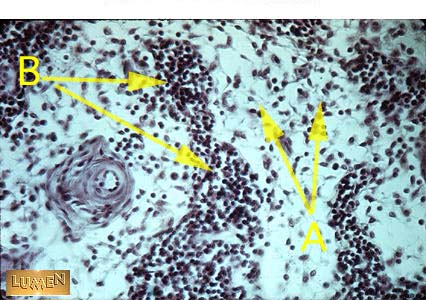

Identify 'A' and 'B'.

Answer A

Medullary Sinus

Answer B

Medullary Cord